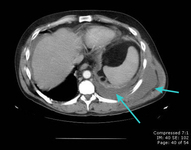

CT scan showing large right pleural effusion

From the collection of Dr Nicholas Maskell; used with permission